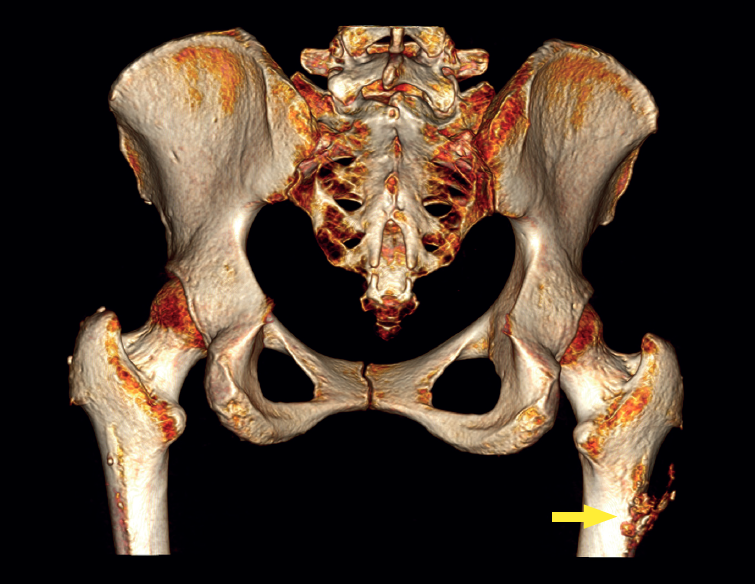

A usual rehabilitation protocol after hip arthroscopy / endoscopy was applied, with crutch-assisted weight bearing for three weeks and circumduction movements plus stationary cycling for 15 minutes, four times a day. The patient was advised to avoid extension and long stride exercises in order to prevent possible gluteus maximus tendon injuries. She reported complete reversal of the symptoms, including the radicular pain, with a return to physical activity and sports three months after surgery. One year after the operation, the patient remained asymptomatic in any activity, with complete disappearance and no recurrence of the calcification (Figure 4).

reacae.31181.fs2402007en-figure4.png